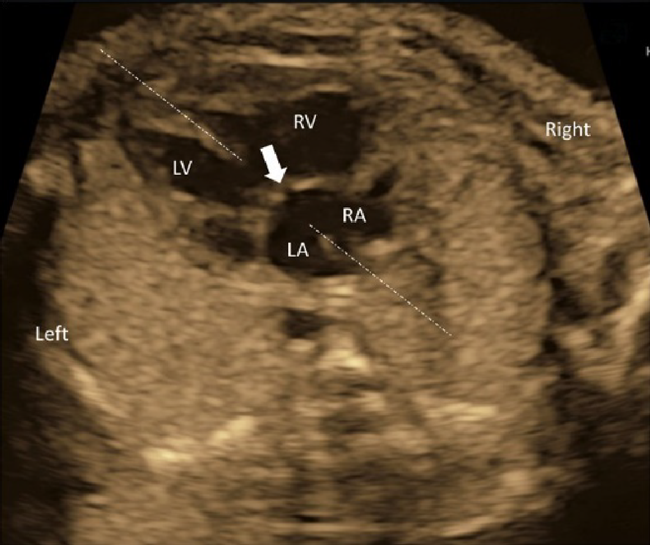

(2) 4CV

- The laterality of the left and the right ventricles can be determined using the 4CV. The right ventricle is characterized by the moderator bands within its cavity.

- The midline of the heart should be scrutinized. An AV septal defect or a large ventricular septal defect can be diagnosed using tomographic ultrasound scans. A small defect would require color Doppler echocardiography.